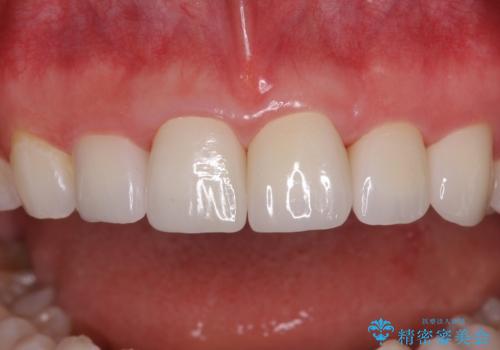

矯正治療にて歯並びを整えた後に、虫歯の大きかった5本の歯をセラミッククラウンにて補綴し、明るい口元になりました。